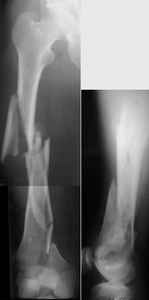

I presented a series of ~25 such cases at EuroTrauma'2004. Many cases were discussed here. I attach am example. Look also recent cases at http://www.hwbf.org/hwb/conf/alex58/scfx.htm,

http://www.hwbf.org/hwb/conf/alex63/alex63.htm

THX, initial images are

1,

2.

At that moment we had in stock only the 10 mm solid nails so of course there was no idea about early weight bearing. But it was quite enough for early knee ROM excersises (see attached). Two locking screws through the distal block provided that.